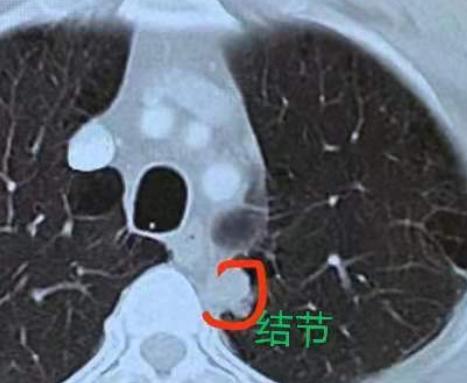

肺多发结节的手术,在我看来,不单是技术活,更像是一门“艺术”!前段时间,有位60